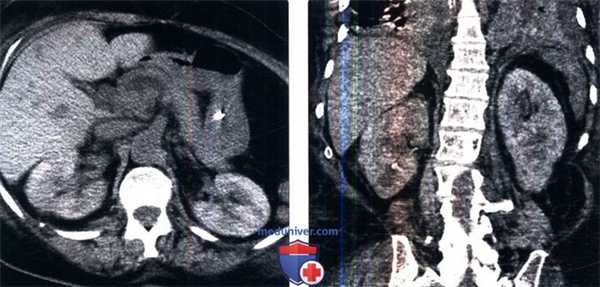

(Слева) КТ без контрастирования, аксиальный срез: у женщины 69 лет, в анамнезе у которой имеется септический шок, определяется отсроченное пятнистое контрастирование почек.

(Справа) На корональном срезе снова определяется отсроченное пятнистое контрастирование почек. За семь дней до этого исследования пациентке был введен йодсодержащий контрастный препарат. У нее имеются множественные сопутствующие заболевания, а креатинин плазмы повысился от 1,5 мг/дл до 3,2 мг/дп, вследствие ОТН, причиной которого, возможно, являются воздействие множества факторов.